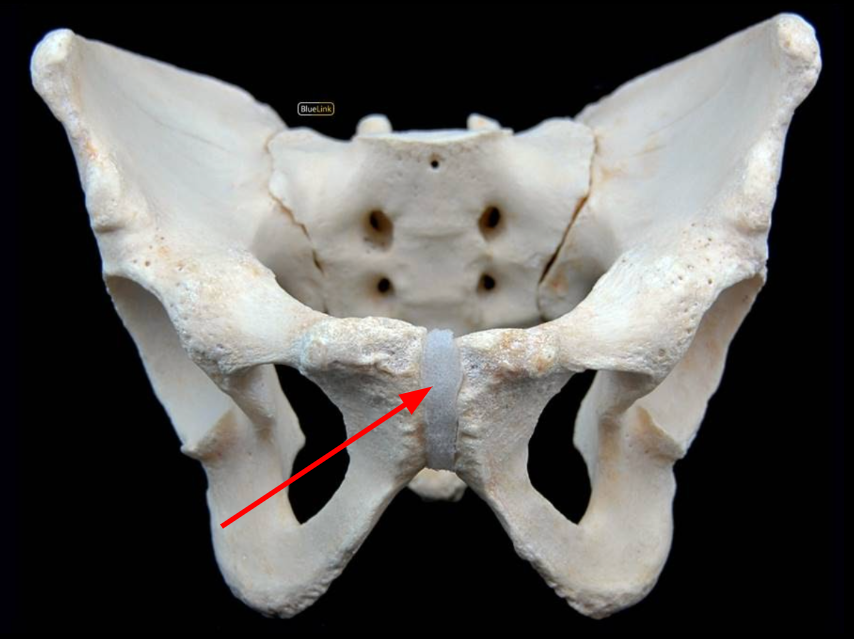

Pubic Symphysis

Ischiopubic Ramus